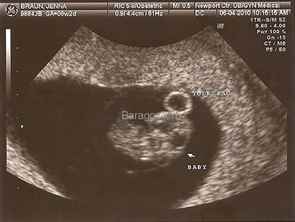

Некоторые специалисты рекомендуют использовать ультразвуковое исследование для более точного определения срока, особенно если менструальный цикл нерегулярный. УЗИ позволяет оценить размеры плода и его развитие, что может уточнить дату родов. Важно помнить, что каждая беременность индивидуальна, и консультация с врачом поможет учесть все факторы, влияющие на срок.

Если же дата зачатия неизвестна, можно использовать данные УЗИ, которые позволяют более точно определить возраст плода. На ранних сроках беременности УЗИ может дать информацию о размере эмбриона, что позволяет установить его возраст с высокой точностью. Обычно это делается на первом скрининговом УЗИ, которое проводится на сроке 6-12 недель. Врач измеряет размеры эмбриона и сравнивает их с нормами для данного срока, что позволяет установить эмбриональный срок.

Акушерский срок наиболее точно можно определить с помощью процедуры УЗИ. Так, проводя обследование, врач смотрит на размер плодного яйца и копчико-теменной размер. На первом УЗИ врач спрашивает у женщины про ее цикл, когда были последние месячные.

Срок беременности врач вычисляет по параметрам плода. У него есть специальная таблица, в которой указаны средние размеры плода в первом триместре. Обычно в этот период дети не отличаются друг от друга в развитии. В следующих триместрах наблюдаются разные показатели параметров малыша, они могут быть выше или ниже, весить больше или меньше, окружность головы также может быть разной. На этих этапах могут быть видны отклонения в развитии.

Итак, с помощью УЗИ врач может поставить наиболее точный акушерский срок в первом триместре. Конечно, иногда врачи могут ошибаться, что бывает редко, но уже во втором триместре врач сможет поставить наиболее правильный срок беременности и вычислить дату рождения с максимальной точностью. Некоторые женщины сталкиваются с тем, что в течение всей беременности предполагаемая дата родов меняется несколько раз.